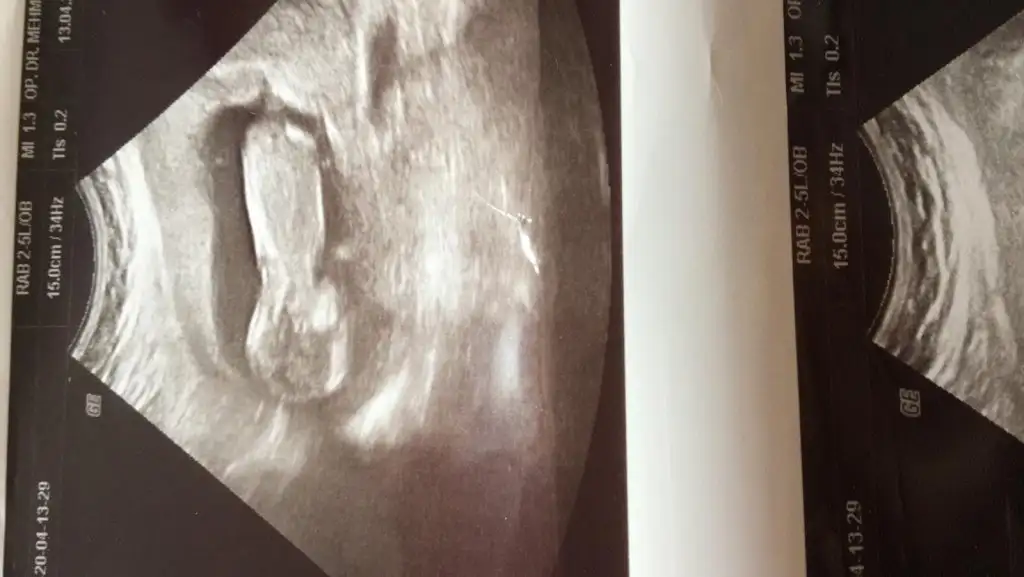

Burada net değil sanki sanki kız11 haftalik hemen yolluyorum.

Ögrendinizmi kızmıMalesef daha öğrenemedik. Dun hastaneye gittim surekli gittigim doktor yoktu. baska bir doktora gorunmek zorunda kaldim. O da şu anki pozisyonundan dolayı göremiyorum dedi... ins kısa zamanda tekrar kendi doktoruma gidecem. öğrenir öğrenmez size haber veririmTesekkur ederim benj hatırlayıp sorduğunuz için

29 nisanda ayrıntılı ultrasonumuz var. malum gundemden dolayi pek hastaneye gidemedigimiz için daha kesin öğrenemedikÖgrendinizmi kızmı![]()